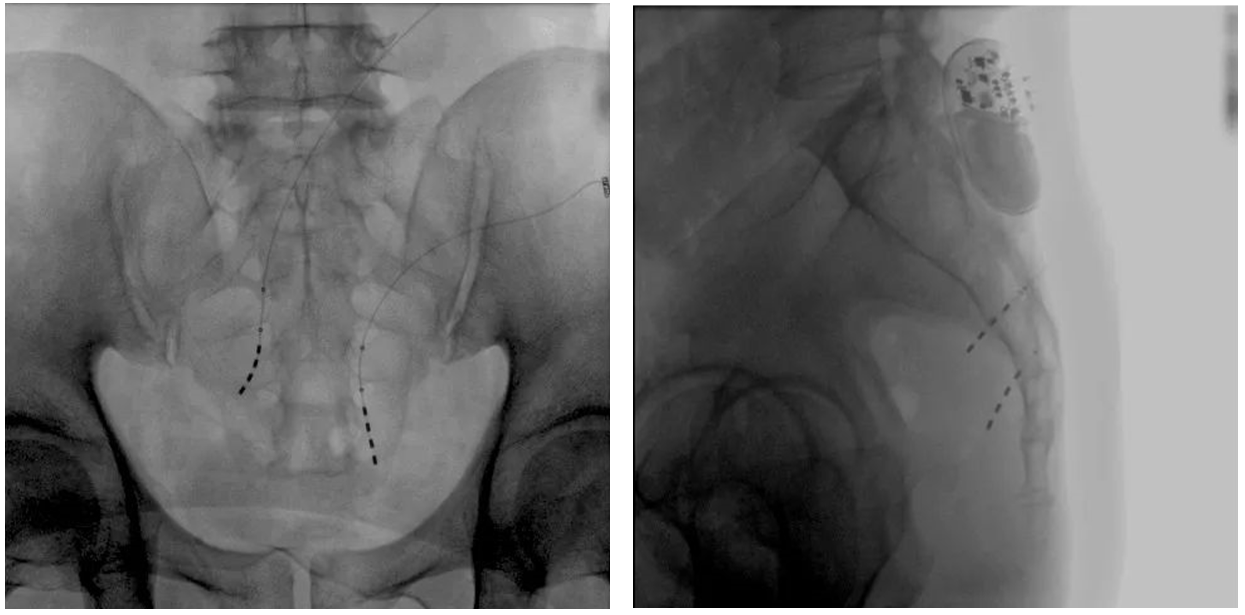

Preoperative imaging of the patient

Intraoperative image of large flat-panel integrated mobile C-arm

In sacral neuromodulation or sacral nerve stimulation (SNS), the physician first inserts electrodes into the sacral foramen 3 through a guide needle under fluoroscopic guidance, and stimulates the nerve fibers and inhibits the detrusor through the stimulation of pulse currents. shrink. In this step, the doctor will first test and evaluate the patient's nerve stimulation response. If the stimulation effect is obvious, it means that the plan can meet the surgical expectations. Next, the doctor will implant a pulse current generator in the nearby subcutaneous fat and connect it to the electrode, so that this part can be stimulated for a long time in the future and improve the symptoms of OAB.